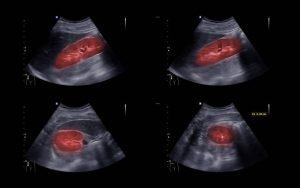

2. Hình ảnh sỏi thận trên siêu âm

Trong khi thực hiện siêu âm, sóng siêu âm sẽ được phát ra từ máy siêu âm và đi qua cơ thể bệnh nhân. Khi sóng siêu âm chạm vào sỏi thận, nó sẽ bị phản xạ lại và được thu nhận bởi các cảm biến trên máy siêu âm. Dữ liệu này sẽ được xử lý để tạo ra hình ảnh sỏi thận trên màn hình máy siêu âm.

Trên hình ảnh siêu âm, sỏi thận có thể xuất hiện như các nốt tăng âm có bóng cản hoặc không, tùy thuộc vào loại sỏi. Sỏi thận nhỏ hơn 2mm có thể không thể thấy trên siêu âm, trong khi những sỏi lớn hơn 10mm có thể dễ dàng được phát hiện. Bên cạnh đó, siêu âm còn có khả năng xác định vị trí và kích thước của sỏi, giúp cho việc đưa ra quyết định về phương pháp điều trị thích hợp.